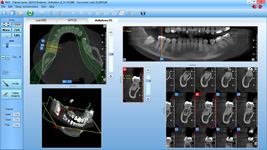

coDiagnostiX – Dental Wings

Jedná se o externí plánovací program, spojený se zubní laboratoří a frézovacím centrem, který využívá dat získaných z 3D rentgenu čelisti, otisku zubů a dásně (scanu zubů a dásně) a finálního návrhu protetické náhrady.

Tento program umožňuje tříprostorovou počítačovou simulaci při plánování pozic implantátů. Součástí programu je i databáze, ve které mohou být uloženy všechny typy implantátů od všech výrobců, včetně jejich délek, průměrů i tvarů.

Lékař si vytvoří všechny typy zobrazení potřebných pro naplánování – tedy 2D snímky (panoramatický), příčné řezy i 3D model.

Vidí zde i důležité anatomické útvary – čelistní dutinu, průběh nervu atd. Po proměření množství kosti – šířky i výšky vybere z databáze vhodný typ implantátu a umístí ho do požadované lokality. Ihned vidí jeho pozici ve všech 3 rovinách a na

všech snímcích i 3D modelu. Může upravovat podle potřeby jeho pozici, sklon atd.

Všechny vybrané a správně umístěné simulované implantáty se ukládají do „počítačové karty“ pacienta s jejich pozicí, délkou, průměrem, typem i sklonem. V programu také lékař navrhuje chirurgické šablony pro řízenou nebo navigovanou implantaci.

Lékař i pacient tedy ještě před vlastní operací vidí, jak by mělo ošetření probíhat a vypadat.